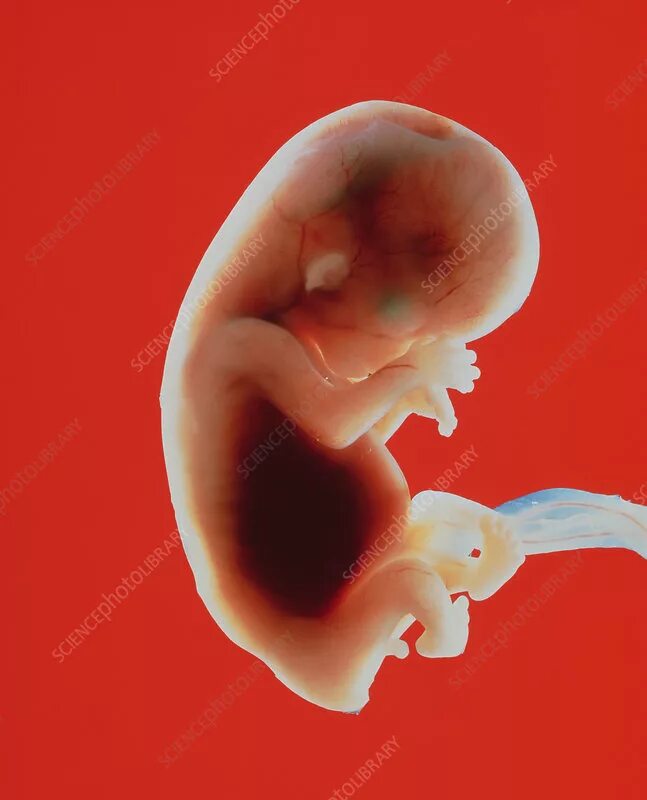

10 week old